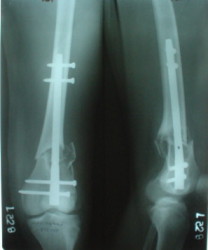

Отправитель: Alexander Chelnokov 28 Декабрь 2003, 21:01

1

2

de> you think you are using antigrade nails for some very low

de> fractures including some intercondylar fractures.

Exactly. It seems the option looks underestimated.

No, i haven't seen such comparisons. However some advantages of closed antegrade nailing vs conventional plating looks self-evident like no site opeining, no bone skeletization, less blood loss, no need for autografting... If you or other colleagues can help me with the references it would be greatly appreciated. I would be interested also to compare ante- vs retrograde nailing for the localization.

I attached an example of C2 fracture with result of the same technique in 5 months.